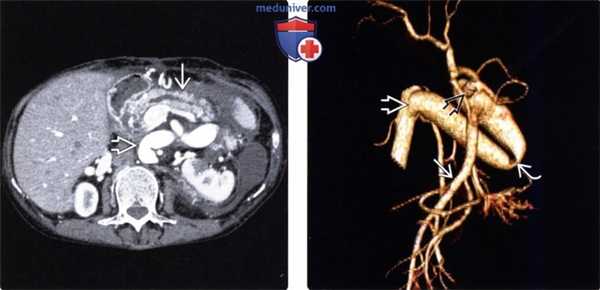

(Слева) На аксиальной КТ с контрастным усилением у пациента после мультивисцеральной трансплантации визуализируются аллотрансплантаты поджелудочной железы и печени. Область аортального анастомоза явно расширена.

(Справа) На КТ-артериограмме (объемный рендеринг) у этого же пациента визуализируется аортальный анастомоз. Определяется перегиб аллотрансплантата аорты под острым углом, который затем делает петлю, что может привести к нарушению кровотока. Обратите внимание на донорскую верхнюю брыжеечную артерию, по которой осуществляется артериальное кровоснабжение аллотрансплантата тонкой кишки, в то время как чревный ствол донора кровоснабжает аллотрансплантат поджелудочной железы и печени.